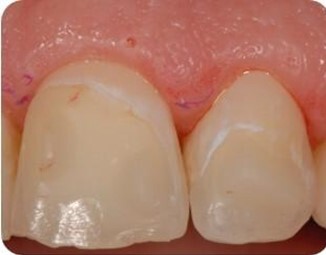

Paziente di 37 in terapia ortodontica con allineatori. Durante la seduta di igiene orale intercettiamo due lesioni cariose iniziali non cavitate intorno agli attachments a livello degli elementi 21 e 22. Dopo aver documentato fotograficamente le lesioni, procediamo con l’applicazione di CurodontTM Repair al termine della seduta di igiene orale e lasciamo trattamento domiciliare con CurodontTM Protect 2 volte alla settimana per 2 mesi.

Pretrattamento CurodontTM Repair

Rivediamo la paziente a distanza di 30 giorni per controllare l’igiene domiciliare e la compliance nell’applicazione del trattamento CurodontTM Protect. Fissiamo la seduta d’igiene distanza di 3 mesi dalla seduta iniziale e la paziente continua il trattamento domiciliare per un altro mese.

Post trattamento CurodontTM Repair a distanza di 30 giorni, con trattamento CurodontTM Protect domiciliare 2 volte alla settimana